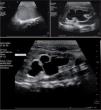

Se trata de un recién nacido hembra de 39 semanas de gestación, de parto eutócico, cuyo peso al nacer es de 3.475g con test de Apgar al minuto de 9 y a los 5min de 10, con diagnóstico ecográfico prenatal de tumoración retrovesical de aproximadamente unos 45mm con ureterohidronefrosis bilateral. La RM fetal mostraba la presencia de probable hidromucocolpos por imperforación del himen con presencia de ureterohidronefrosis bilateral (fig. 1). La ecografía a las 12h de vida mostró la presencia de tumoración pélvica que corresponde a cavidad vaginal llena de líquido espeso, así como ureterohidronefrosis bilateral (fig. 2). A las 24h de vida se realiza himentomía, que da salida a abundante líquido lechoso y espeso. La analítica efectuada a las 48h de vida mostró unas cifras de urea, (15mg/dl) y creatinina (0,5mg/dl) dentro de límites normales. La exploración física, así como el resto de las exploraciones complementarias realizadas descartaron la presencia de otras anomalías anogenitales o urológicas.